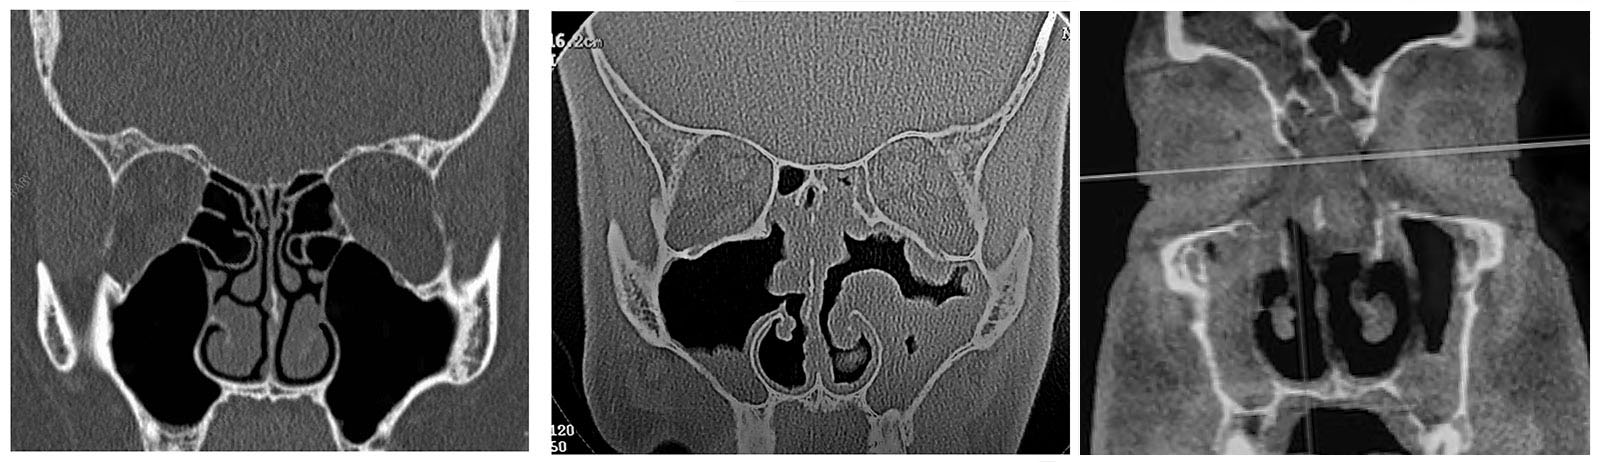

On the left, a CT scan of normal sinuses as if the patient is facing you.

In the middle, a 2003 CT scan of the author’s sinuses, showing his congestion even after operations in 1990 and 2000.

Much of the blockage there is not mucus but instead saggy sinus tissues no longer able to shrink due to constant allergic inflammation.

On the right, a June 2025 CT scan of the author's sinuses. This time his congestion was mostly polyps

(as he'd been focused since his 2010 operation on keeping his sinuses as clean as possible via saline use).